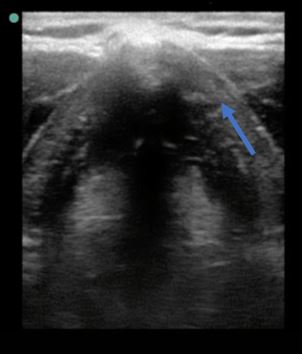

¿Qué estructura es señalada en las siguientes imágenes?